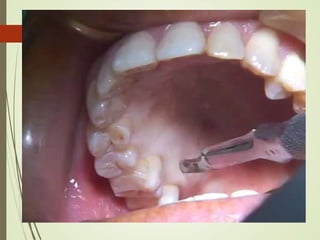

1. CLASSICAL TECHNIQUE

9/25

• Graft thickness was originally outlined by Sullivan and Atkins

in 1968.

• Thin or intermediate thickness grafts: Increasing zone of

keratinized tissue (Soehren et al 1970).

• Thick or full thickness grafts: Root coverage and ridge

augmentation procedures 8/25